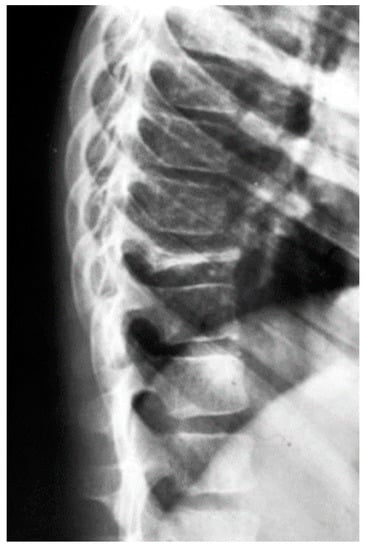

- Kaeser, M.A.; Kettner, N.W.; Albastaki, U.; Kotb, H.A.; Eldesouky, I.M.; Pierre-Jerome, C. Tuberculous Spondylitis Presenting as Severe Chest Pain. Clin. Pr. 2012, 2, 42. [Google Scholar] [CrossRef]